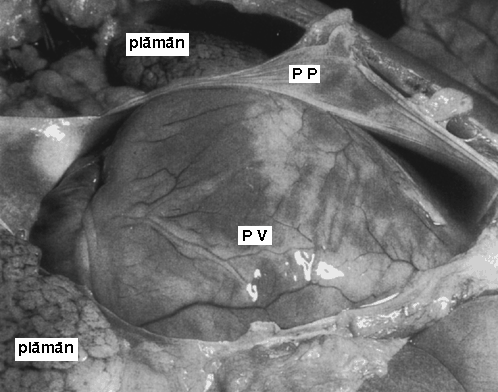

Traumatisme si leziuni

Traumatism abdominal inchis Trusa de lavaj peritoneal Citeste tot ... 951 cuvinte

Dimensiune mica

+ cu imagini |